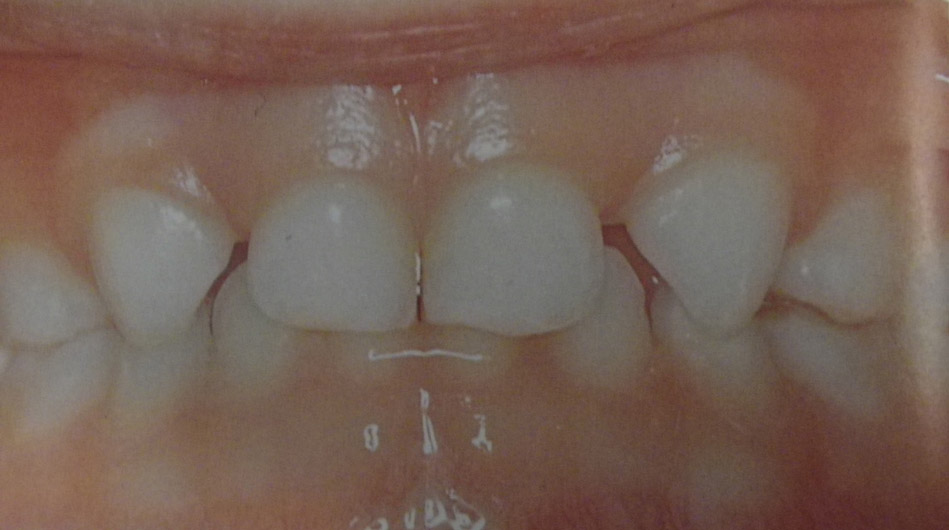

Ανωμαλίες αριθμού, θέσης και σχήματος νεογιλών και μονίμων δοντιών

Υπάρχουν διάφορες καταστάσεις που χρήζουν διάγνωσης και θεραπείας από τον παιδοδοντίατρο. Δείτε τις μία προς μία κάνοντας κλικ στις παρακάτω εικόνες.